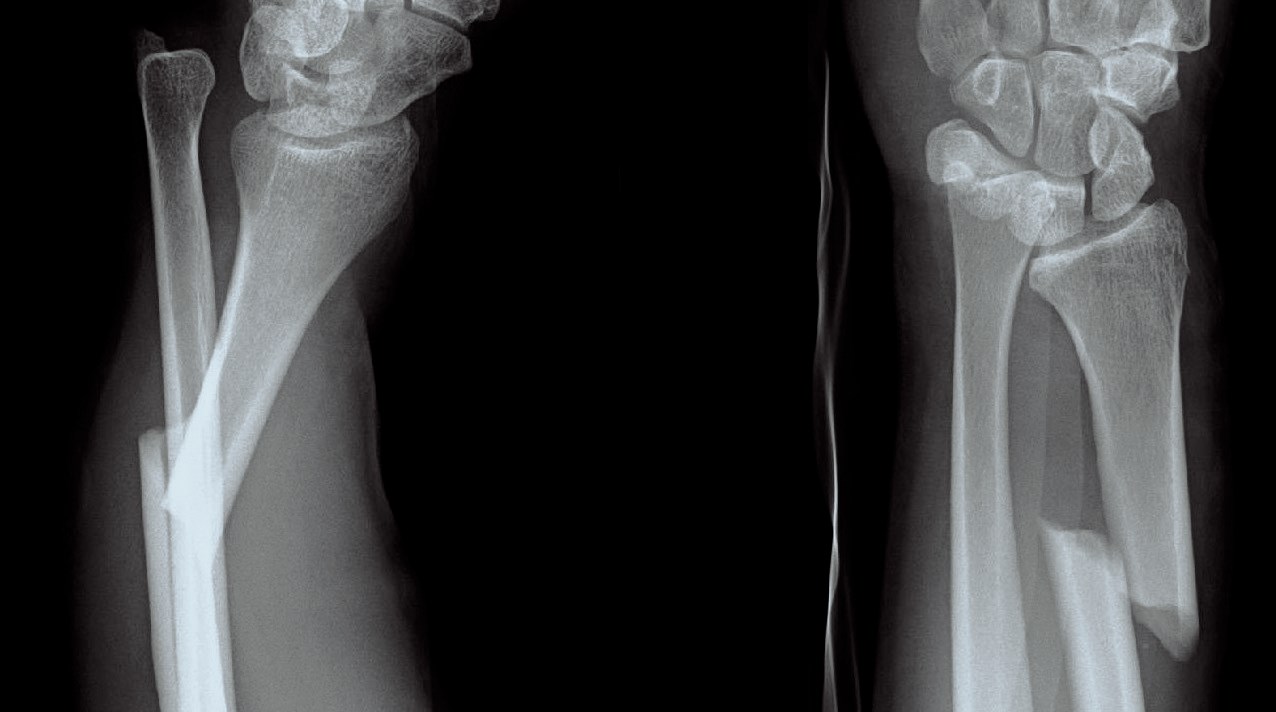

Scaphoideumfraktur

Symtom

Palpationsömhet i fossa Tabatiére, smärta vid axialt kompression av tummen samt vid dorsalextension respektive radialdeviation av handleden.

Drabbar ofta yngre individer i samband med sportutövning eller efter annat kraftigt dorsalextensionsvåld. Frakturen är ofta svår att identifiera på slätröntgen varför upprepade undersökningar och/eller CT/MR kan behövas.

Scaphoideum är dåligt vaskulariserad och ofta läker dessa frakturer (ffa proximala polfrakturer) långsamt; 3 månader i gips är normaltid! Gipsen skall immobilisera tumbas, handled och begränsa armens pro-supination. Utebliven läkning (pseudartros) är relativt vanligt och risken ökar om frakturen inte immobiliseras från skadetillfället.

Vid misstanke om scaphoideumfraktur (adekvat trauma, ömhet i fossa Tabatiére)

- Immobilisera i scaphoideumgips även om röntgen bedöms normal.

- Beställ då röntgenkontroll (utan gips) efter 10-14 dagar! Om röntgen är u a även efter 2 veckor, men status kvarstår: ordna snar MR- eller CT-undersökning!

Om skadan missas leder den mycket ofta till pseudartros och senare artros. En smärtsam pseudoartros kräver ofta att man tillför ben från crista illiaca vid operation och vid en handledsartros krävs någon typ av steloperation eller annat större ingrepp.

Det är tyvärr vanligt att frakturen missas då patienten kan uppleva symtomen som en distorsion, men det är också ganska vanligt att det missas av den undersökande doktorn. Detta sammantaget (s.k. 'patient's and doctors’ delay') innebär tyvärr att pseudoartrosoperationer är ganska vanliga.